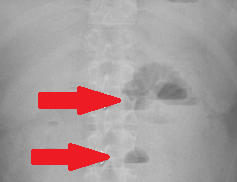

Red arrows — transition point. Multiple air-fluid levels (Courtesy Dr. V. Penopoulos)

Plain abdominal radiograph. Nonspecific findings of intestinal obstruction (Courtesy Dr. V. Penopoulos)